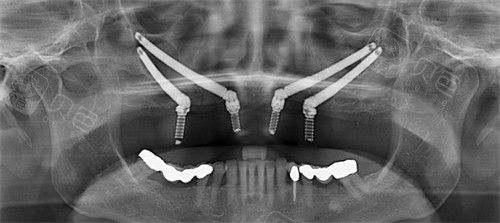

穿颧穿翼种植牙并非普通的牙科手术,它是针对上颌骨极度萎缩、无法通过常规植骨手术修复的患者而研发的高端技术。穿颧种植是将特长的种植体植入到面部的颧骨中,而穿翼种植则是将植体固定在上颌骨后方的翼突处。

这两个部位的骨质密度极高且结构稳定,即便牙槽骨已经流失殆尽,也能为种植体提供强大的支撑力。

穿颧穿翼种植示意图

在植体长度上,普通种植体长度通常在八毫米至十四毫米之间,而穿颧种植体由于需要横跨上颌窦到达颧骨,其长度往往达到三十毫米至五十毫米。在手术难度上,普通种植属于基础外科,而穿颧穿翼则属于颌面外科的范畴,对医生的解剖学功底要求极高。

其次是设备投入,此类手术通常需要配备智能化导航系统、高清三维CT以及实时监测设备,以确保植体能更准一些避开眼眶、神经和血管。